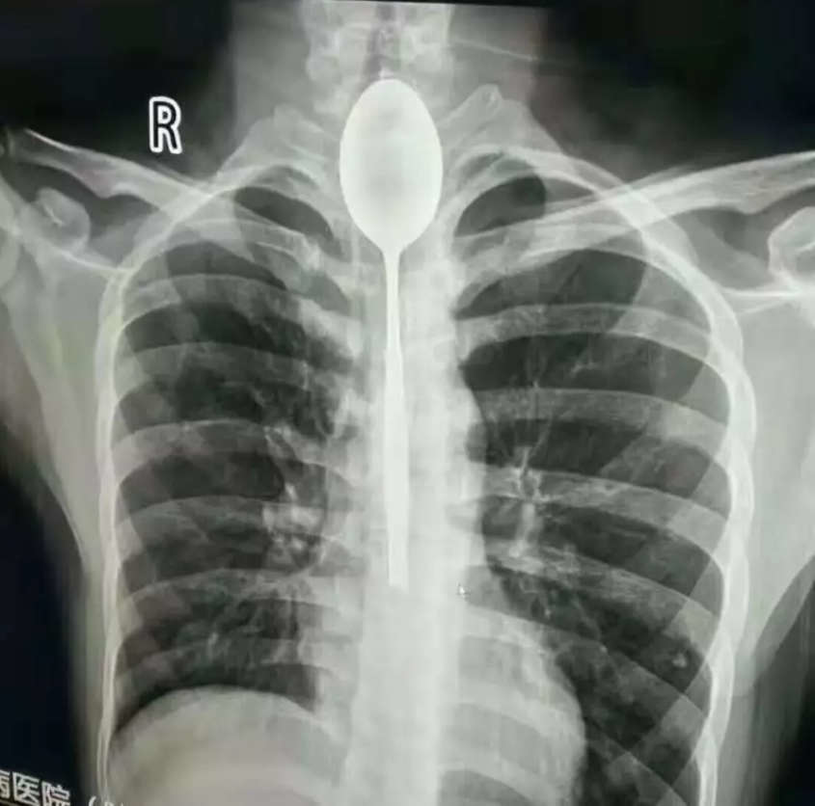

Phẫu thuật lấy…thìa trong thực quản bệnh nhân

Bệnh viện Đa khoa Xinjiang Meikuang (Tân Cương - Trung Quốc) vừa phẫu thuật thành công và lấy ra một chiếc thìa dài 20 cm, nằm suốt 1 năm trong thực quản bệnh nhân 21 tuổi. Năm 2017, anh Pan Zhang ở Tân Cương cá cược với bạn bè rằng sẽ nuốt một chiếc thìa. Đã nói là làm, anh nuốt một chiếc thìa kim loại dài 20 cm. Tuy nhiên chiếc thìa đã không lọt xuống dạ dày mà nằm lại ở phần trên thực quản. Điều đáng ngạc nhiên là anh Pan Zhang không cảm thấy đau đớn khó chịu gì khi chiếc thìa nằm trong thực quản trong suốt thời gian 1 năm. Chỉ đến thời điểm vừa qua, khi chiếc thìa bắt đầu va đập vào lồng ngực, anh mới cảm thấy đau ngực dữ dội và phải nhập viện cấp tốc…